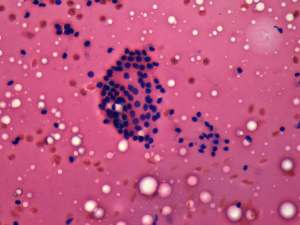

Aspiration cytology resulted in benign, colloid goiter.